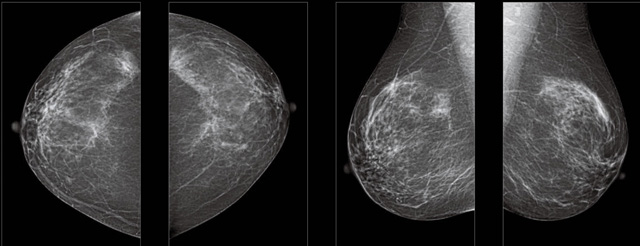

首先不同年齡階段的乳腺篩查頻次種類不一樣。青春期女性第二性征明顯發(fā)育開始,每個月進行自我乳腺檢查。20-30歲的女性就不推薦進行乳腺檢查,因為年輕女性的乳腺組織非常緊急。鉬靶X光線等檢查的射線不能辨別腫塊跟腺體。身體就白吸收了輻射,影響了身體健康。每個月自檢一次就是在洗澡時候,對著鏡子看看乳房外觀正常,皮膚潰爛、腫塊、顏色改變、再摸一下有沒小疙瘩。乳腺高危人群,特別是有乳腺CA遺傳傾向的女性,乳腺導管跟小葉不典型增生,原位癌。30歲前有乳房放療的女性。乳腺癌篩查可以把年齡提前到40歲前。40到70歲的女性可以在適合的機會篩查。

采用影像檢查技術來發(fā)現(xiàn)疑似特定病檢查跟人群的普查。一到兩年進行一次X光線的乳腺檢查。記過是C或者D型,可以加上B超協(xié)同。還可以一年一次核磁共振MRI檢查。70歲以上的女性認為絕經的女性是比較安全的。實際上也有乳腺癌的風險。65歲以上風險也很大。也是需要進行機會性篩查。